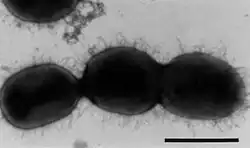

Brackiella es un género de bacterias gramnegativas de la familia Alcaligenaceae. Actualmente contiene una sola especie: Brackiella oedipodis. Fue descrito en el año 2002. Su etimología hace referencia al patólogo alemán Manfred Brack. El nombre de la especie hace referencia al tamarino Saguinus oedipus.[1] Es aerobia e inmóvil. Tiene un tamaño de 0,9 μm de ancho por 1,1 μm de largo. Catalasa y oxidasa positivas. Forma colonias ligeramente rugosas, y de color blanco en agar TSA tras 2 días de incubación y de color grisáceo en agar sangre, sin hemólisis. No crece en agar MacConkey. Temperatura óptima de crecimiento de 37 °C. Es sensible a amikacina, ampicilina, cefotaxima, cefoxitina, ceftazidima, cloranfenicol, ciprofloxacino, gentamicina, kanamicina, ácido nalidíxico, tetraciclina, estreptomicina y trimetoprim-sulfamerazina. Se ha aislado del corazón de un tamarino, posiblemente con endocarditis.

| Brackiella oedipodis | ||